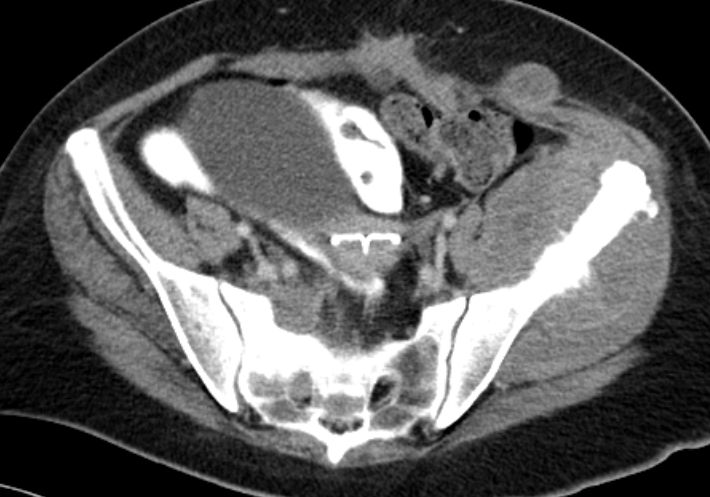

| Beispiele bildgebender Diagnostik von primären Colonkarzinomen | Zökum |

| Beispiele bildgebender Diagnostik von lokalen Metastasen | Lymphknotenmetastasen![]() |

mesenteriale Metastasierung |

peritoneale Metastasierung | |